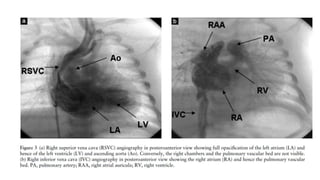

• The diagnosis of SVC to LA in this particular case was made by cardiac

catheterisation in which the green dye injected in SVC appeared in

Femoral artery after few seconds, while also, the catheter could be

seen traversing from SVC to LA.